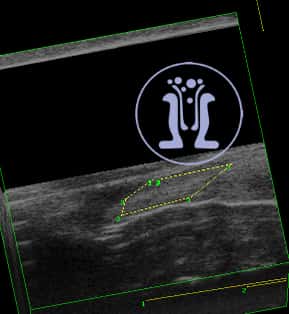

Ασθενής γυναίκα με φλεγμονή στο πεπτικό, προσέρχεται με αδυναμία στην συγκράτηση των κοπράνων. Στο ιστορικό της αναφέρει εγχείρηση με την μέθοδο του Ιπποκράτη. Ανευρίσκονται μετεγχειρητικές αλλοιώσεις του έξω σφιγκτήρα.